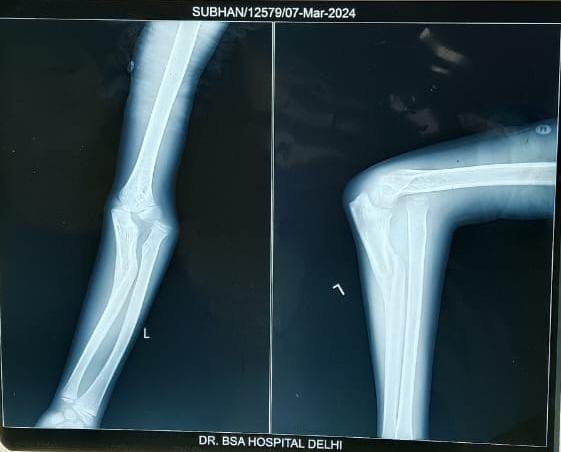

This retrospective review included eight patients presenting with NMF at the orthopedic outpatient department of our institution, characterized by proximal ulnar fractures with persistent radial head dislocation for more than 4 weeks after the initial trauma. Inclusion criteria consisted of delayed surgery beyond 4 weeks, radiological evidence of unreduced radial head dislocation, and clinical findings such as pain, deformity, or functional restriction requiring operative correction. Patients were excluded if they had acute Monteggia injuries, a history of previous elbow surgeries, ongoing site infections, or pathological fractures. At the time of presentation, time of injury, Bado’s classification, range of motion (ROM) at elbow, and Mayo Elbow Performance Index (MEPI) score were noted. Informed consent for corrective osteotomy was obtained from the guardian of the patient. All corrective procedures were performed by the same orthopedic team under general anesthesia using a standardized surgical approach. Before surgery, each patient underwent a comprehensive clinical assessment to document general health status, mechanism of injury, and any accompanying trauma. Radiological confirmation was achieved through anteroposterior and lateral X-rays of the forearm and elbow. A radial head dislocation was defined if the longitudinal axis of the radial neck did not intersect the central third of the capitellum on the lateral view. When doubt persisted, additional lateral X-rays were obtained in varying positions (supination, pronation, or extension) (Fig. 1). Pre-operative investigations included hematological and biochemical profiles, renal function tests, electrolyte estimation, blood glucose levels (fasting and postprandial), electrocardiography, and chest X-ray.

Figure 1 : Pre-operative radiograph showing Bado’s type 1 neglected Monteggia fracture.